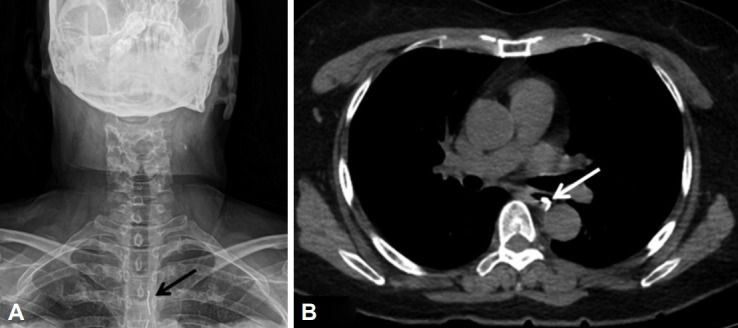

Esophageal Rupture Occurred During the Endoscopic Removal of a Lodged Denture.